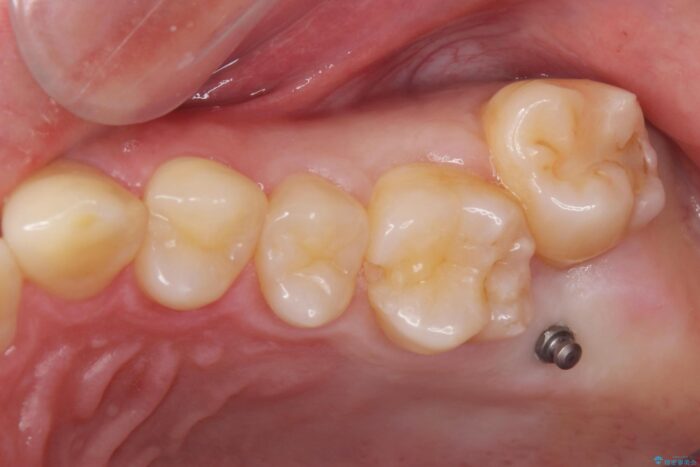

左上の奥歯がシザーバイトがありました。

部分矯正を行いシザーバイトを改善した後、インビザラインで歯列を整えました。

シザーバイトは歯と歯が噛み合っていないのでしっかり噛めるように処置をする必要があります。